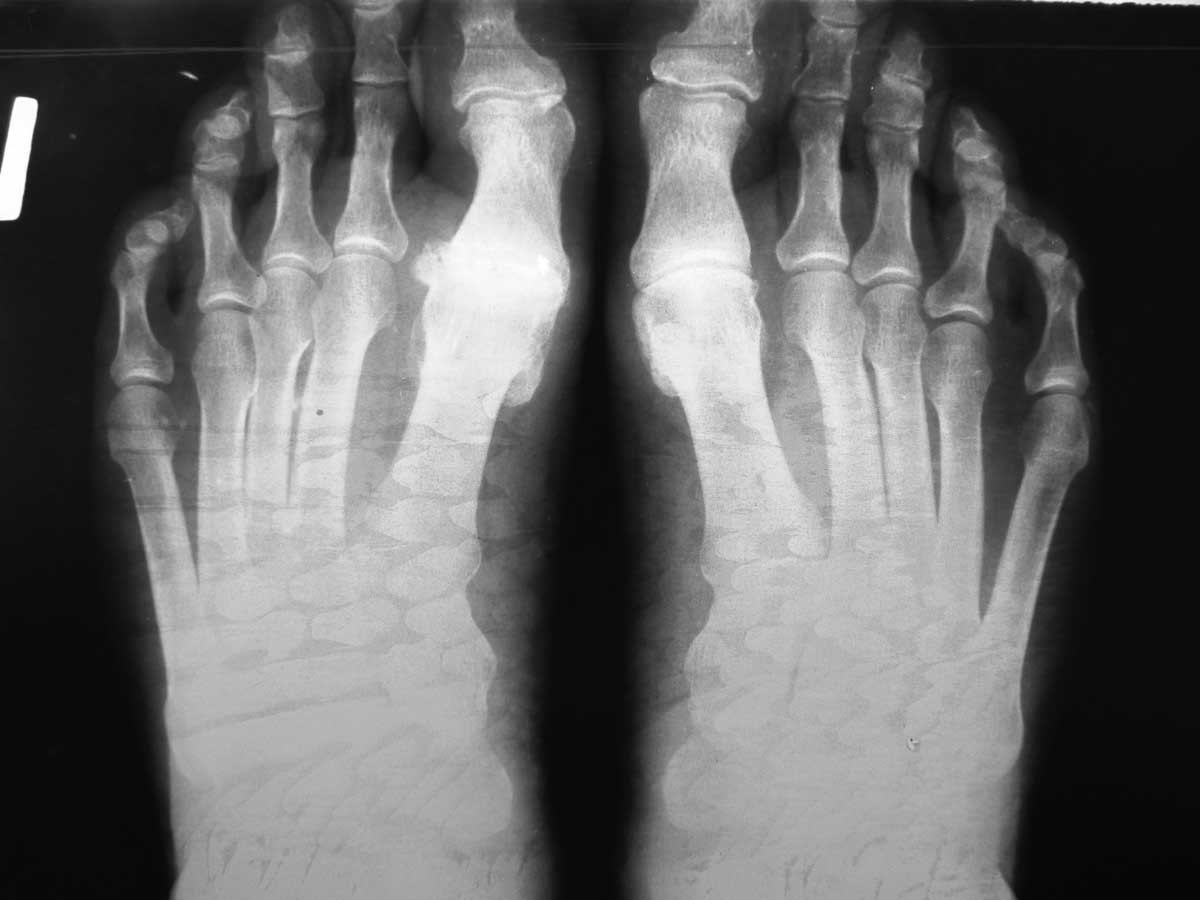

Здравствуйте, коллеги. Помогите с тактикой дальнейшего лечения.Мужчина 52 года, активный физически. В марте 2012 оперирован по поводу ДОА плюсне-фалангового сустава 1 пальца, сделана резекция основания основной фаланги и остеофитов головки плюсневой кости. Послеоперационное лечение: массаж, физиотерапия. В настоящее время беспокоят сильные боли в суставе, сохраняется ограничение движений. Дальнейшая тактика: артродез ПФС?, Эндопротезирование ПФС?, повторная резекция основной фаланги? Мнения наших коллег разделились. На фотографиях: вид стопы в настоящее время, рентгенограммы до операции, после операции, в настоящее время. Прошу прощения за неважное качество снимков.

Любой из рассматриваемых Вами вариантов имеет право на жизнь. Наиболее вероятная причина болей - слишком экономная резекция фаланги: адекватная декомпрессия сустава не достигнута. Протезирование 1 ПФС у молодого активного физически мужчины предполагает ревизию уже через несколько лет. Так что артродез или повторная резекция основной фаланги - равнозначные оптимальные варианты.

У больного 1 плюсневая кость длинее 2 (в этом основная причина развития патологии). Молодой активный пациент с высокими требованиями, считаю, что эндопротезирование более оптимальный вариант. Эндопротезирование явлеяется альтернативой артродезу (который можно сделать всегда, но движений не будет уже) и артропластике (после которой рецидив будет очень быстро). Эндопротезированием можно восстановить и объем движений и функцию.

Причинами неудовлетворительного результата могли стать следующие: 1) недостаточная величина резекции основной фаланги и 2) "стирание" оставшегося хряща головки 1 ПК опилом фаланги. В своей практике обычно убираем больше кости (примерно 1/4 - 1/3 длины фаланги), опил моделируем, укрываем лоскутом капсулы или Артелоном (специальный биодеградируемый скользящий материал).

Наилучшим вариантом представляется вар. 2, так как сохраняется собственная головка 1 ПК, которая хорошо переносит нагрузки (а в фазу заднего толчка на неё приходится до 70% веса человека). Имеем достаточно много отдалённых результатов: амплитуда движений в 1 ПФС 30 - 45 градусов, болевой синдром не беспокоит.